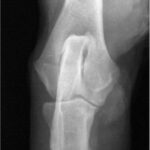

- A los 4-6 meses, si no hay ningún síntoma, es suficiente realizar una única radiografía mediolateral en posición neutra, o sea en 90-100º de flexión.

- Si hay síntomas (cojera), o si en la ML hay alteraciones (o si no estamos seguros) realizaremos siempre otra proyección mediolateral en flexión (45º) y una anteroposterior (lo ideal: ligeramente oblicua con 15 grados de pronación, o sea rotación interna)

- A los 12 meses de edad, para el informe definitivo, necesitaremos SIEMPRE una pr. mediolateral en extensión no forzada 110-140º, y una anteroposterior estándar.